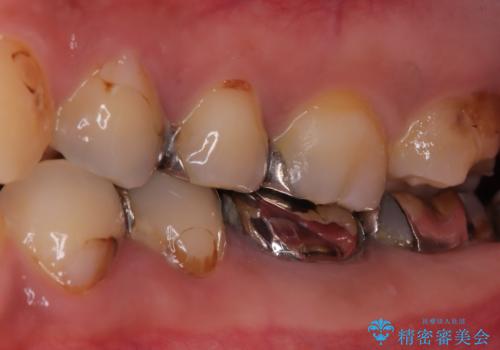

- 左下4番の奥歯に、歯肉の下まで進行した深い虫歯を認め来院されました。通常であれば神経を抜く必要があるほど深い虫歯でしたが、患者様の歯をできる限り保存するため、歯の神経を抜かずに残すことを目指す治療計画を立案。歯肉の下にある虫歯を適切に治療するため、歯周外科処置で歯肉のラインを調整した上で、精密なセラミッククラウンで修復することになりました。

まず、虫歯を徹底的に除去するために、歯周外科処置で歯肉のラインを調整し、治療部位を露出させました。その後、神経に近接した深い虫歯を慎重に除去。神経の保護処置を施し、歯の神経を抜くことなく保存することができました。型取りから、患者様の歯の色や形に合わせたオーダーメイドのセラミッククラウンを作製。最終的に、精度の高いクラウンを装着し、咬み合わせを細かく調整しました。これにより、神経を温存しながら、虫歯の再発を防ぎ、快適な咬み心地を取り戻していただけました。